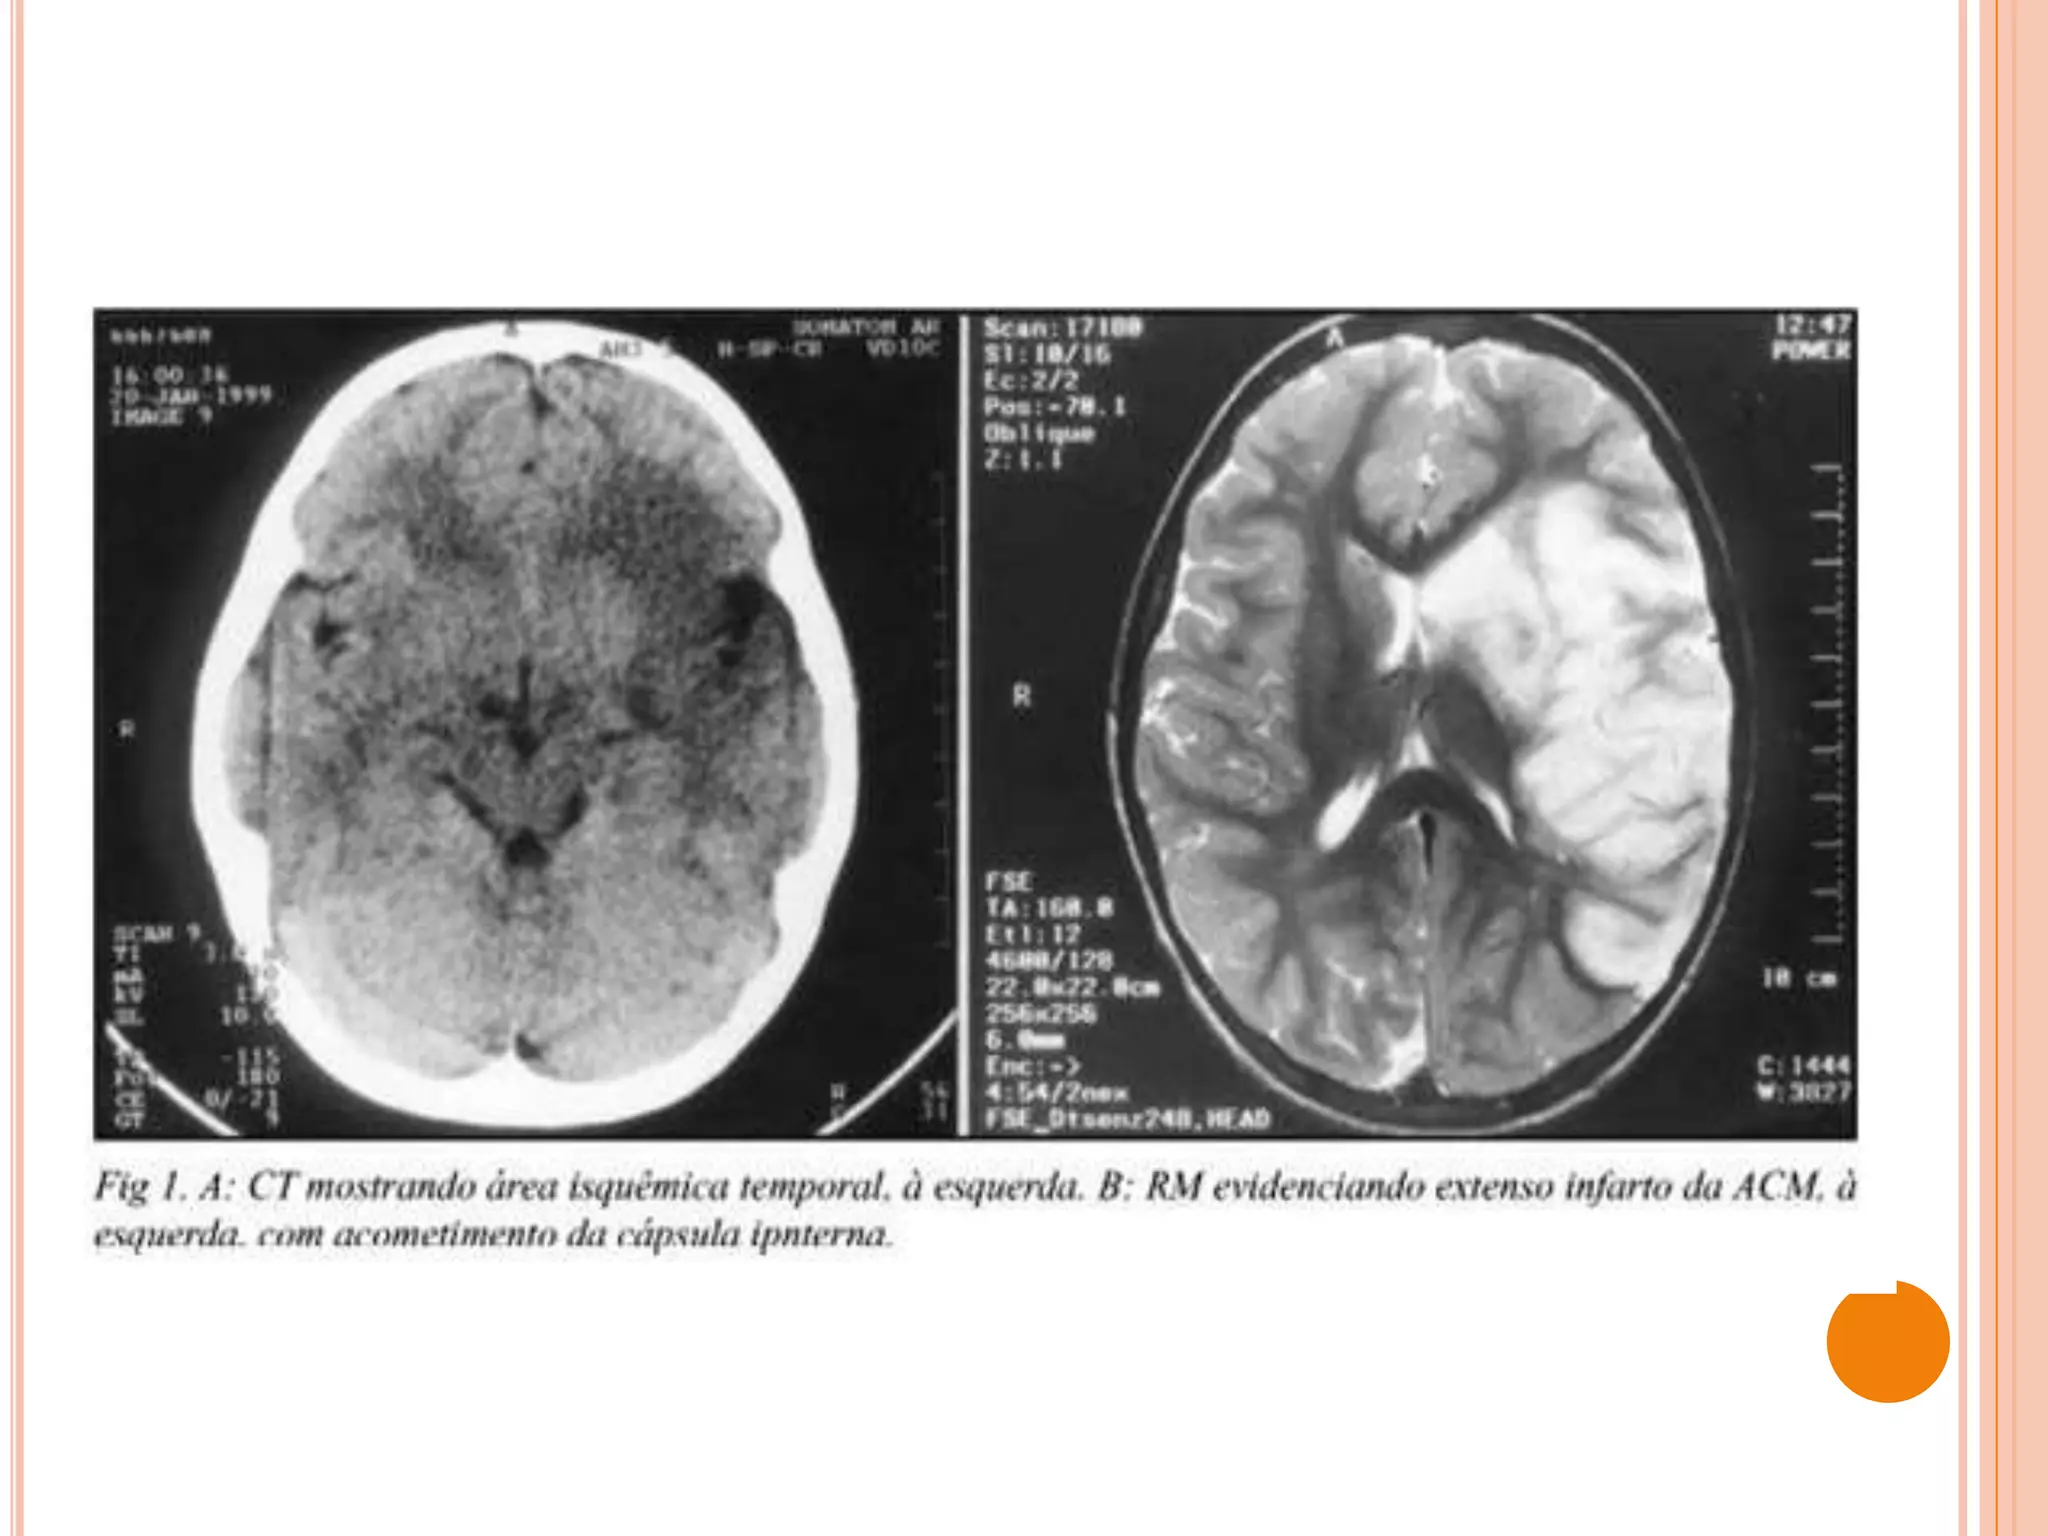

 Tomografia Computorizada (TC)

 Imagiologia por Ressonância Magnética (IRM)

 mais sensível que a TC no diagnóstico precoce de enfarte cerebral

 Ressonância magnética (RM), técnicas de difusão e perfusão

 RM mais sensível no diagnóstico de enfarte